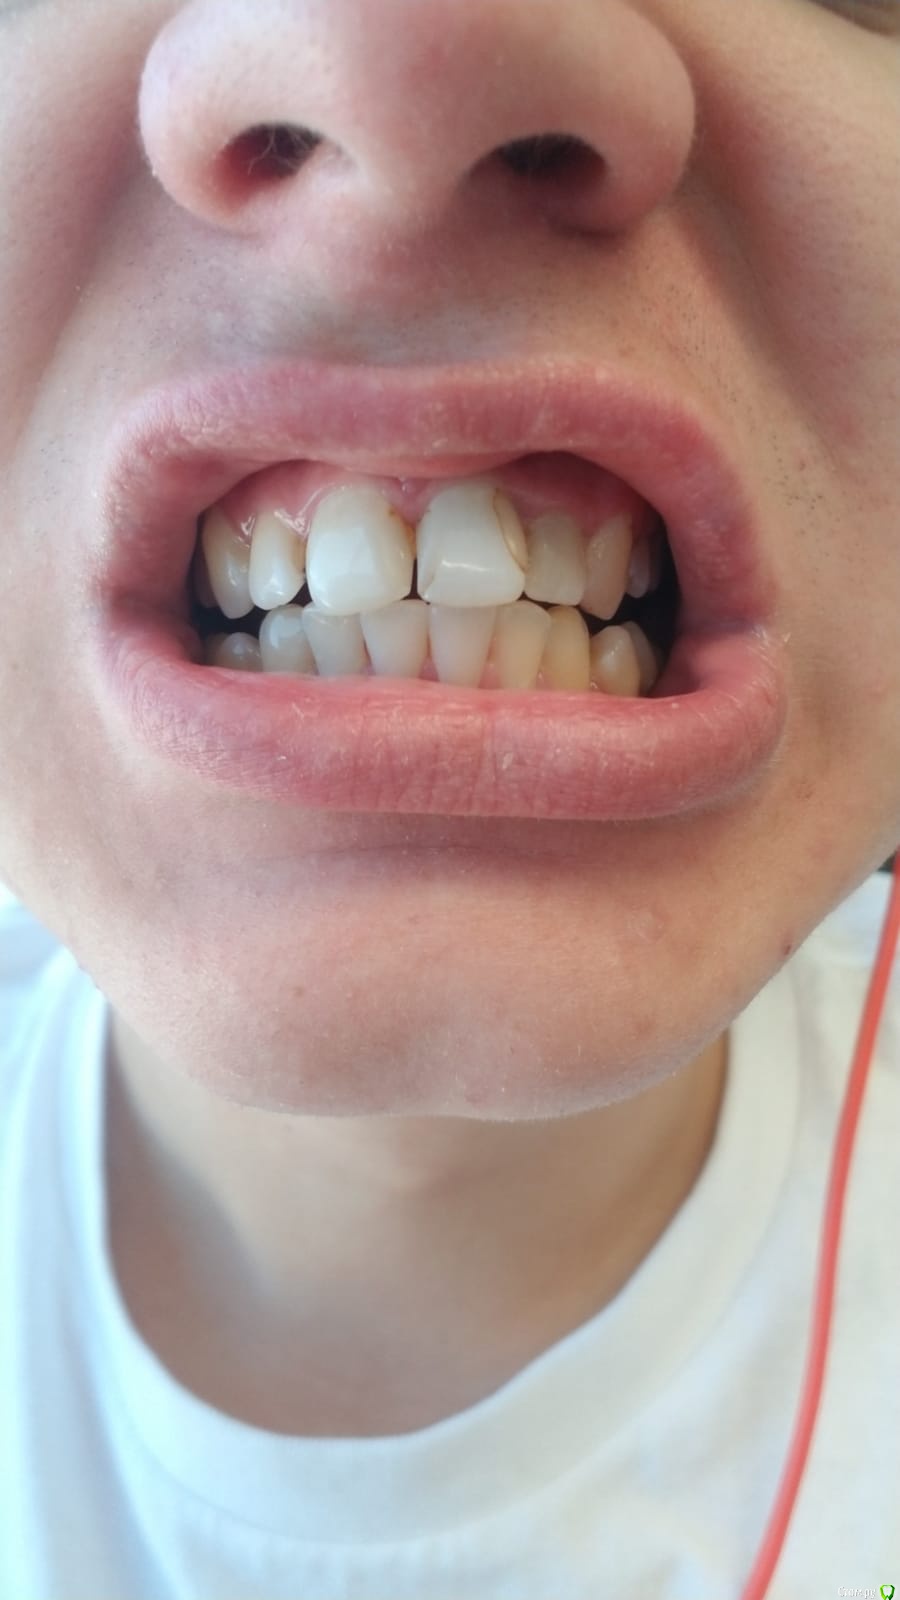

Svettala Опубликовано 5 февраля, 2020 Поделиться Опубликовано 5 февраля, 2020 (изменено) Добрый день,уважаемые стоматологи. Молодому человеку (23г) требуется эстетика на передние зубы. Врач предлагает поставить четыре слитных коронки сразу (не в России), но нас это предложение смущает и по приезду в Россию думаем протезироваться здесь. Насколько будет правильно и возможно ли поставить коронки отдельно на каждый зуб или хотя бы слитно по две штуки? Что лучше ставить-металлокерамику или циркониевые? Прикус неправильный, знаем, но сейчас пока нет возможности этим заняться. Виниры тоже не рассматриваются. Спасибо за уделенное время.Ps: передние зубы "мертвые", нервы удалены примерно 6-7 лет назад. Изменено 5 февраля, 2020 пользователем Svettala Ссылка на комментарий

red_butler Опубликовано 5 февраля, 2020 Поделиться Опубликовано 5 февраля, 2020 К сожалению, пока нет снимка. Только фото.по фото я не вижу показаний к 4 коронкам Ссылка на комментарий

red_butler Опубликовано 5 февраля, 2020 Поделиться Опубликовано 5 февраля, 2020 Спасибо, я поняла, пока не будет rg снимка, нельзя точно сказать сколько потребуется коронок.сделайте фото со стороны неба, и конечно нужен Rg, но проблем сделать раздельные коронки нет Ссылка на комментарий

red_butler Опубликовано 5 февраля, 2020 Поделиться Опубликовано 5 февраля, 2020 извините, что даст снимок со стороны неба и как лучше его одному сделать)))? позволит оценить степень разрушения зубов, фотографируйте через зеркало Ссылка на комментарий